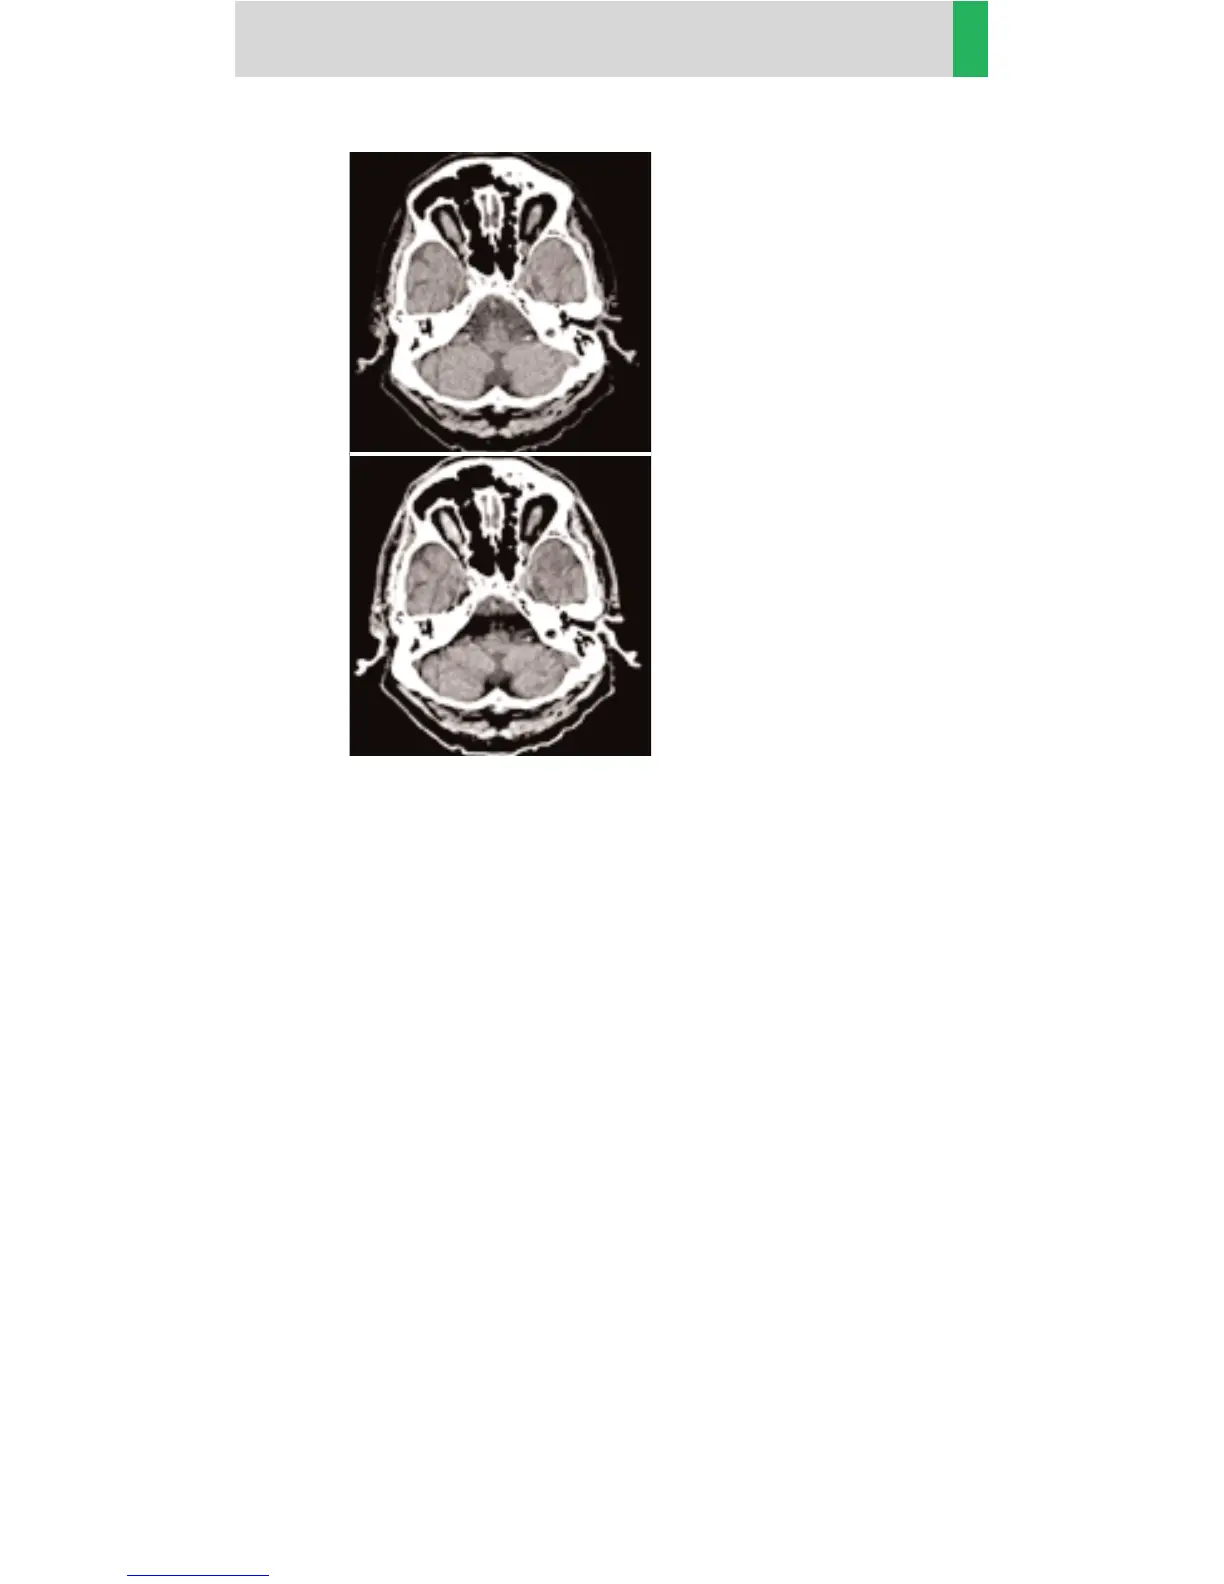

Reconstruction

with PFO filter.

without PFO filter.